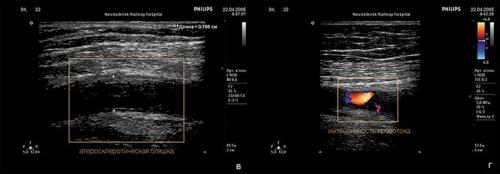

Морфологическим «носителем» атеросклероза являются так называемые атеросклеротические бляшки: плотные образования круглой или овальной формы, белого или желтовато-белого цвета, которые, возвышаясь над поверхностью внутренней оболочки сосудов, суживают их просвет. Наиболее часто фиброзные бляшки обнаруживаются в брюшной аорте и в отходящих от нее ветвях, а также в артериях сердца, мозга, почек, нижних конечностей, сонных артериях и др.

На ранних этапах бляшка представляет собой тонкую соединительнотканную капсулу, в которой содержится много липидов. Это так называемые желтые , или ранимые , бляшки. Последнее название очень точно, поскольку тонкая оболочка этих бляшек может быть повреждена в результате действия как гемодинамических факторов (перепадов давления в сосуде), так и особых белков, вырабатывающихся клетками иммунной системы, которые находятся вблизи оболочки капсулы.